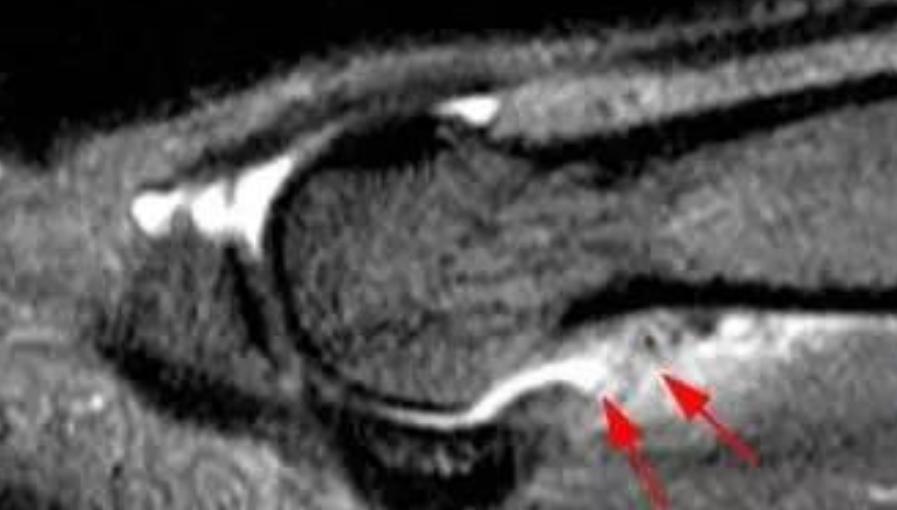

对患趾病史询问和体格检查对诊断至关重要。医师需要对第1跖趾关节的肿胀、瘀斑、畸形进行详细检查。对关节背侧、跖侧关节需要进行触诊检查。并且通过内外翻应力试验和前后方的抽屉实验来检查关节的稳定性。另外还应该检查关节的活动度。背伸时的阻力减少也表明了跖侧结构的损伤。对蹲趾背伸、跖屈力量的评估可帮助检测相关的韧带。现在用MRI来评估草皮趾的损伤程度已越来越常见。